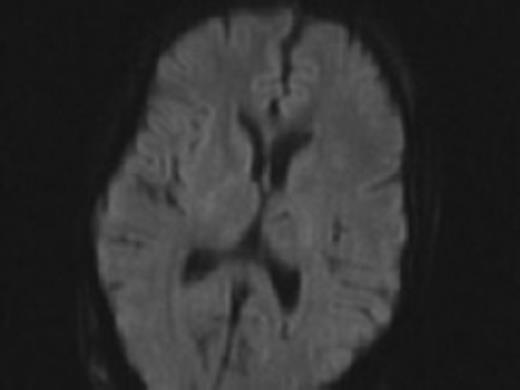

Difussion MRI of the brain prior to syndrome showing no areas of stroke.

We report the case of a 34-year-old woman with a history of pilocytic astrocytoma resection and radiotherapy with ventriculoperitoneal shunt placement as a child who presented with altered mental status and nausea. She was found to have acute hydrocephalus without any pathology noted on MRI (Fig. 1). She was found to have a shunt fracture at the level of the neck and was taken to the operating room for shunt revision (Fig. 2). At this time, she had an entirely new shunt placed including a programmable valve with an anti siphon device. Post-operatively she did well and was discharged home.